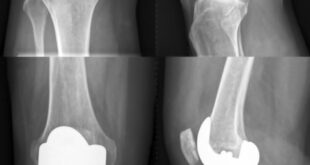

Read More »Adult Reconstructive Surgery: Knee and Hip Replacement

Dr. Sandeep Bhandari did his graduation from Grant Medical College and Sir JJ Group of Hospitals, Mumbai, India. He did his Masters in Orthopedic Surgery from Manipal Hospital Bangalore, India. During his residency, he developed interest in Adult Reconstructive Surgery and did Fellowship at ISAKOS Training Center, Pune, India, headed …